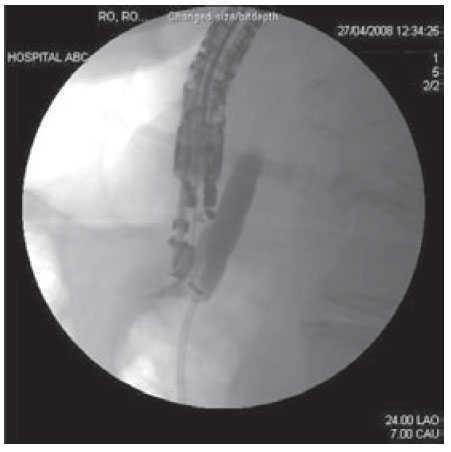

The echoendsocope was placed in the duodenum and was oriented to visualize the extreahepatic biliar system. Color Doppler was used to identify regional vasculature. CBD was punctured under continuous endosonographic guidance using a 22- Gauge needle (Echo tip Ultra; Cook Medical Inc. Winston-Salem NC). To confirm successful biliary access, bile was aspirated through the needle followed by biliary opacification instilling contrast under fluoroscopy. (Figure 2). A 0.018 inch guide wire (Glidewire; Microinvasive Endoscopy, Boston Scientific Corp) was inserted through the EUS needle and advanced in an antegrade fashion, into the duodenum across the papillary orifice.

Figure 2. Fluoroscopic image showing opacification of the common bile duct after gaining access into the common bile duct under continuous endosonographic guidance using a 22-Gauge needle.